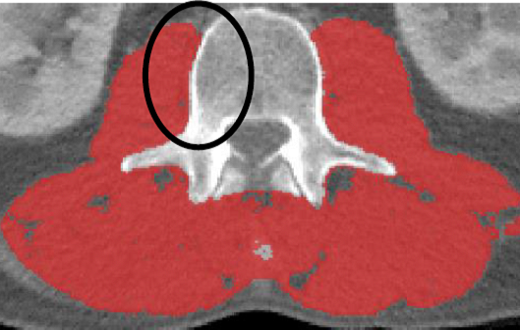

·The area underneath the vertebrae should remain untagged

·If the neural spine is present in the L3, the area underneath the neural spine should remain untagged